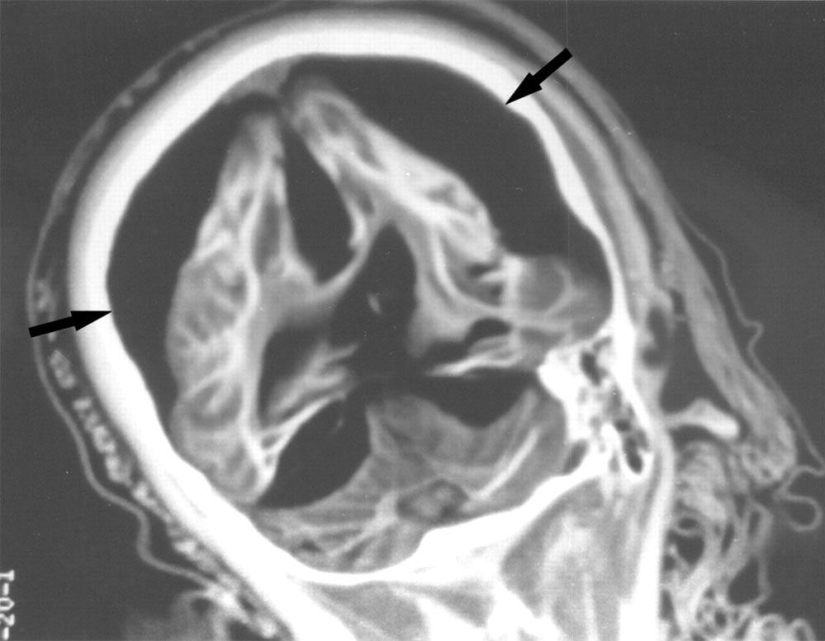

Una radiografía del cerebro de una niña de 15 años muestra que hay una separación entre la materia blanca y gris del cerebro. Las flechas apuntan al aire que rodea el cerebro.